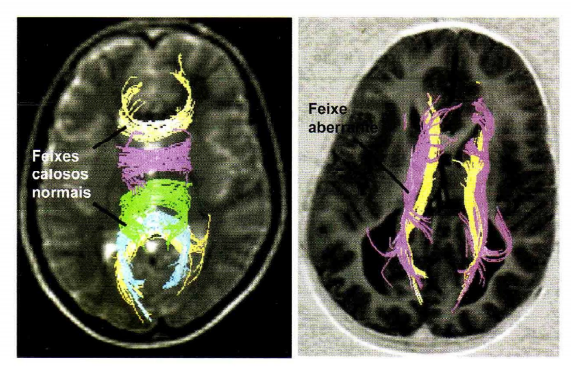

1. Disgenesia do corpo caloso

• estruturas de fibras que interconectam os hemisférios.

1. não há a sinalização adequada para indicar o caminho dos cones das fibras axônicas

1. axônios calosos pioneiros continuam seu trajeto no mesmo hemisférios

1. feixe longitudinal aberrante